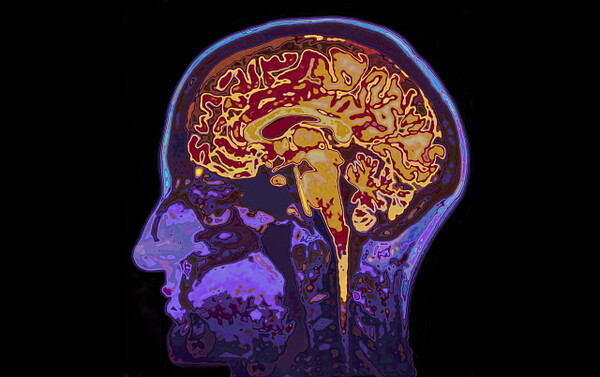

이번 연구 대상자는 심정지 생존자 122명. 이들을 심정지 후 6시간 이내(초기)와 72~96시간(아급성기) 두 시점에서 각각 뇌 MRI를 시행하고, 뇌속 물 분자의 확산 정도를 분석했다.

연속 MRI 기반 겉보기 확산계수(ADC)로 정량 분석한 결과, 심정지 후 72~96시간(3~4일) 시점의 영상이 질환 경과를 가장 정확하게 예측할 수 있는 것으로 나타났다.